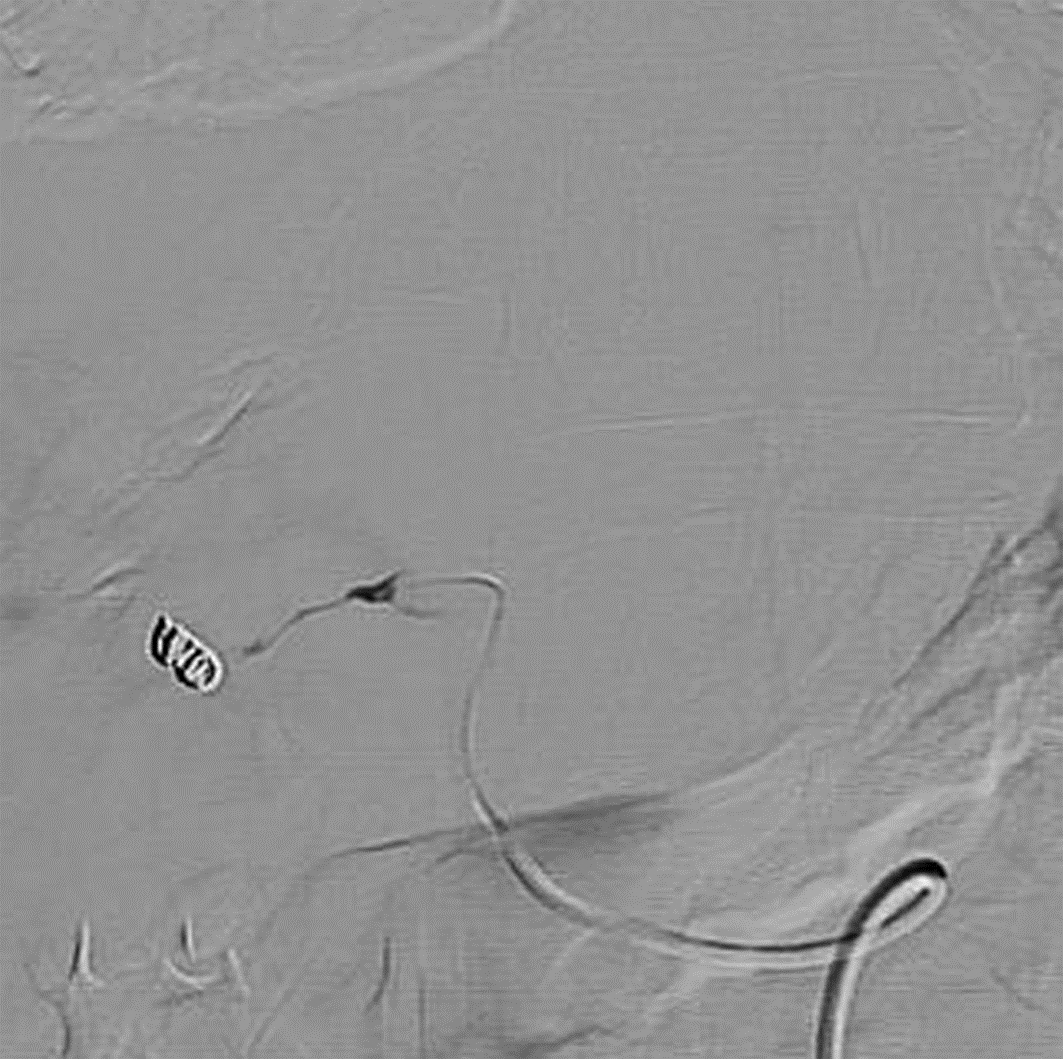

Diagnosis and treatment of hepatic pseudoaneurysm with bile leakage and bile duct hemorrhage after transplantation of donor liver with right hepatic artery variation: A case report

Tian HAN, Rui ZHANG, Zhiyong SHI, Li ZHANG, Jun XU

2022, 38(12): 2818-2820. DOI: 10.3969/j.issn.1001-5256.2022.12.024

Abstract(1759) HTML (1058) PDF (2268KB)(66)